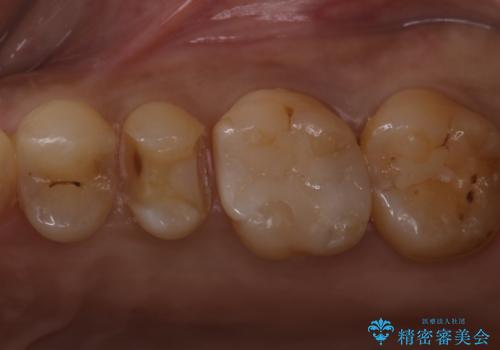

- 歯が欠けたということで来院された患者様です。

診断した結果、昔つめたプラスチックの材料が劣化し割れてしまったことが原因でした。

そのためセラミックれの治療を進めました。

前詰めていたやつをきれいに取り、セラミックにすることによって適合のいいものになりました。色も満足していただけました。